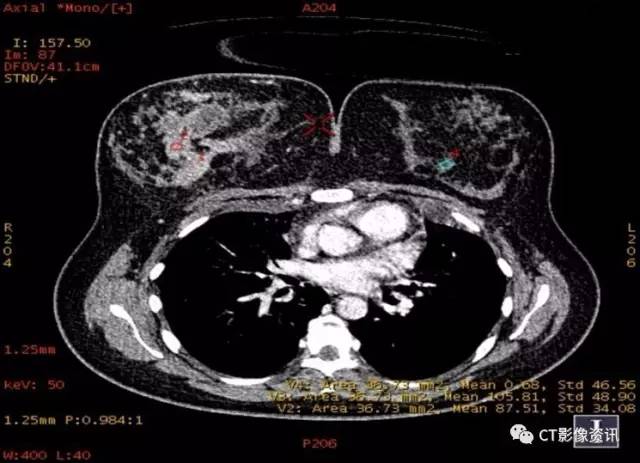

最佳单能乳腺软组织成像(此病例乳腺成像最佳单能在40-50kev之间)

患侧乳腺(右侧)肿大,腺体致密,乳腺呈多发结节样肿块改变,同侧乳内动脉明显扩张。